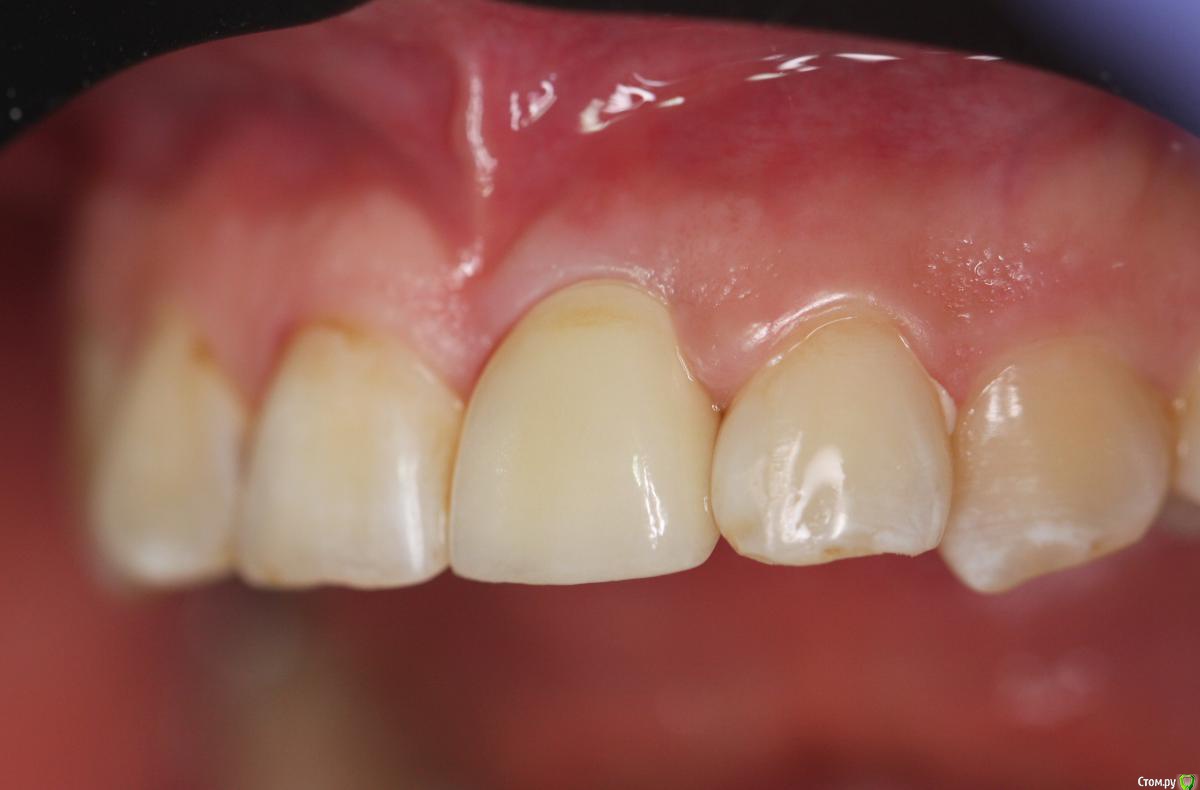

Zorrro Опубликовано 29 февраля, 2016 Автор Поделиться Опубликовано 29 февраля, 2016 (изменено) Через два дня пациент меня неприятно удивил.И ,безусловно,правильно было бы отменить операцию и ограничиться удалением,но… Вот такой был сюрприз под носом с нечищенными зубами.Обговорив риски,перекрестившись начали.Во время операции фото не делал.Слизистая в проекции 21 была сильно истончена острым гнойным процессом,буквально светилась.в итоге после эвакуации гноя промыл фурацилином,установил анкилос А11,подсыпал остеопласт вестибулярно и укрыл это всё сст из бугра в качестве мембраны.ещё один сст пошёл навременный абатмент в виде "шашлыка".Через 10 дней Через 4 месяцас рекомендацией замены пломбы на 12 у своего доктора мы ипопрощались.пациентка осталась глубоко удовлетворённой,а это главное. Изменено 29 февраля, 2016 пользователем Zorrro 4 Ссылка на комментарий

Игорь Пеликан Опубликовано 29 февраля, 2016 Поделиться Опубликовано 29 февраля, 2016 (изменено) Вообще,то есть совсем. Если вестибулярной пластинки не бьіло,на кт похоже нет,и вьі засьіпали ету полость остепластом без ауто ,то ее и сейчас там нету,только мясо,из за етого и рецессия Изменено 29 февраля, 2016 пользователем Игорь Пеликан Ссылка на комментарий